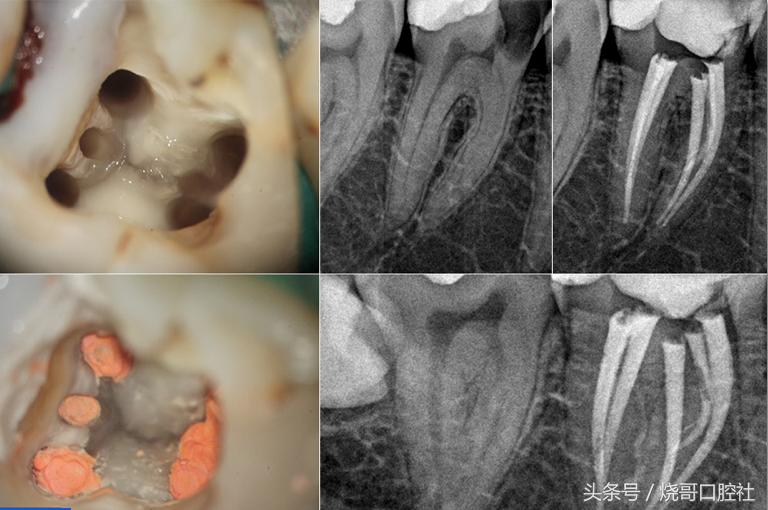

蛀牙过深牙本质被破坏,牙齿变黑而且还会剧痛,说明牙髓已经死去,牙体需要保护就得杀死牙神经,再用生理盐水冲洗,封药消炎几次,关注换药期间将拔髓针拔一下,检验是否有残髓,才可以做氢氧化钙和氧化梓双层垫底,再继续填充纳米树脂。